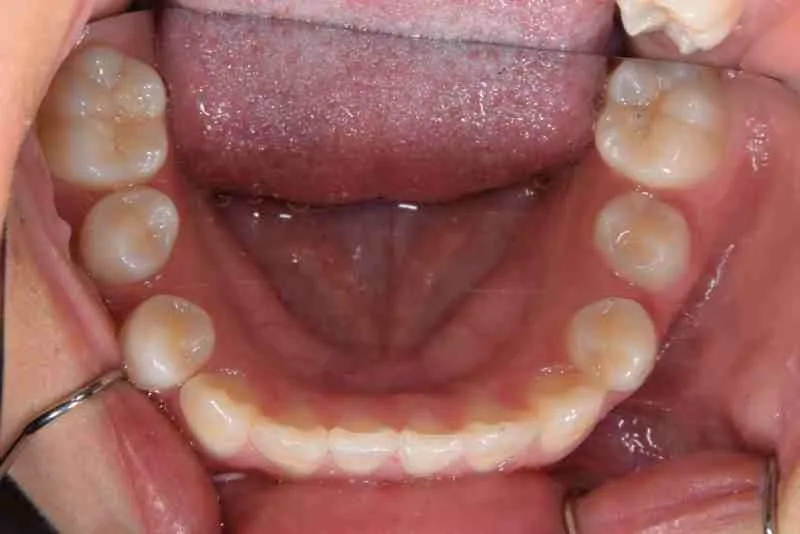

• 治療終了後

治療終了後

先ずは萌出スペースを確保してから開窓術を行い、犬歯を正しい方向へ誘導しました。

マルチブラケット装置は使わずに、最低限の必要な装置を使って目立たないように治療しました。

治療回数29回、2年10ヶ月の治療期間で矯正治療を終了しました。

主訴が改善され、ご満足頂きました。